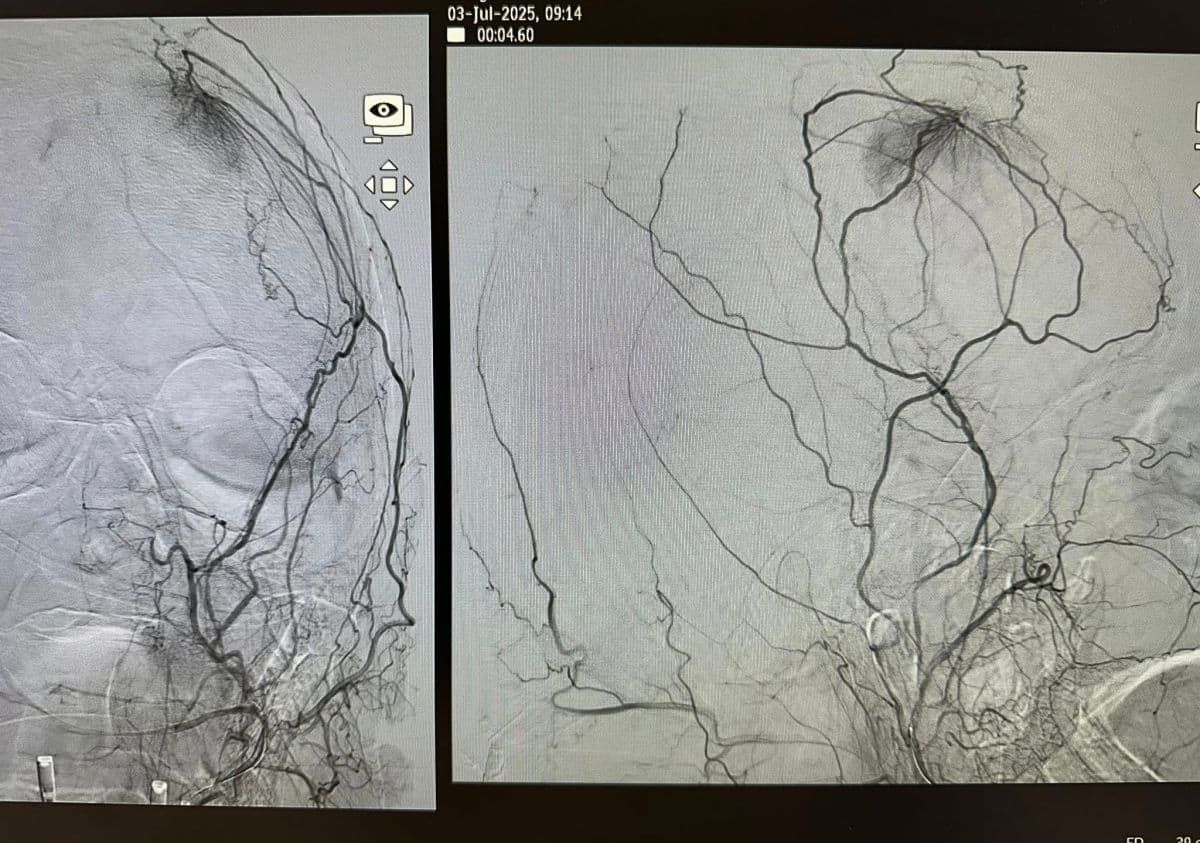

Presurgical Embolization of Brain Meningiomas reduces intraoperative hemorrhagic events and fascilitates surgical excision (Professor of Neurosurgery and Endovascular Neurosurgery V. Panagiotopoulos & Professor of Interventional Neuroradiology P. Zampakis).